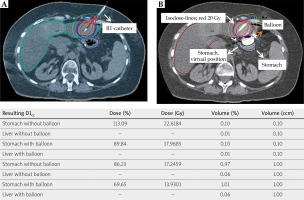

Fig. 2

Planning transversal CT scan with isodoses, prescribed dose to D100 CTV 20 Gy: A) CT-scan without balloon, one BT-catheter inserted; B) CT-scan with BT-catheter and one balloon-catheter inserted